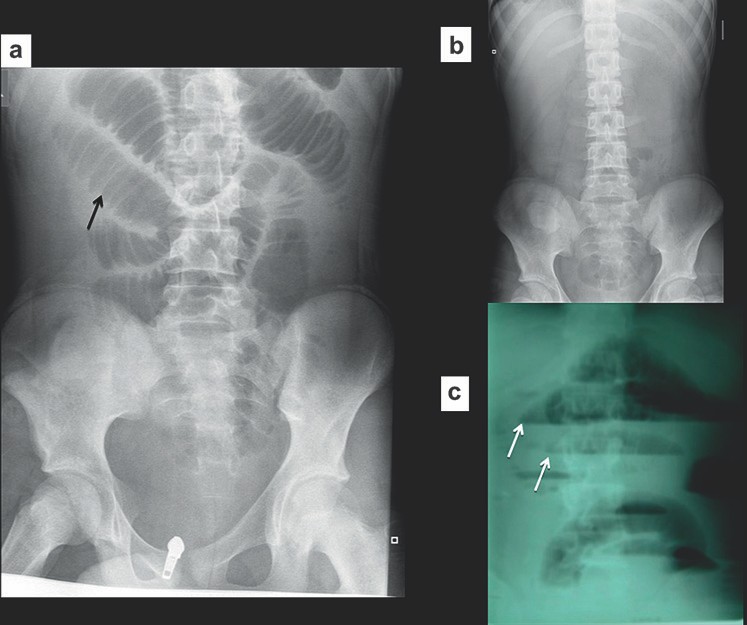

Các dấu hiệu trên phim thường quy là các quai ruột non bị giãn, đường kính trên 30 mm ở đoạn gần và trên 25 mm ở đoạn xa. Các mức khí dịch có chân rộng hơn 25mm là bất thường, các mức khí-dịch của một quai ruột ở các độ cao khác nhau (hình bậc thang) và các bóng khí bị kẹt giữa các quai ruột giãn (dấu hiệu hình tràng hạt) cũng là dấu của hiệu tắc ruột. Ít phổ biến, nếu các quai ruột bị giãn chứa đầy dịch thì phim X quang bụng cho thấy các quai ruột trong ổ bụng rất ít khí làm tăng nghi ngờ tắc ruột ở bệnh nhân có triệu chứng lâm sàng. Các dấu hiệu X quang có thể xuất hiện trước các triệu chứng lâm sàng từ 6 đến 12 giờ. Hình 1 cho thấy một vài dấu hiệu X quang của tắc ruột non.

Hình 1. Tắc ruột non. (a) Nhiều quai ruột non giãn, chứa đầy khí. Lưu ý nhiều nếp vòng theo chu vi ruột. (b) Rất ít khí do ruột non bị tắc chứa đầy dịch. (c) Phim X quang bụng chụp đứng cho thấy nhiều mức khí dịch-hình “bậc thang”.